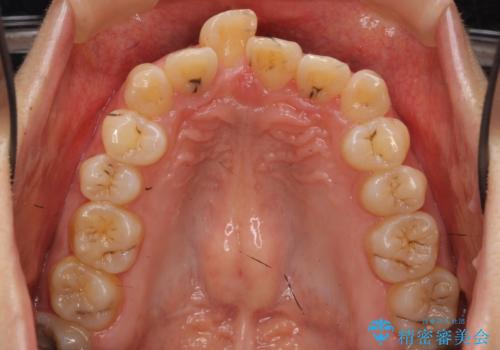

- 前歯の突出を主訴に来院。

上の奥歯を後ろに下げて治療をしました。

矯正用のミニスクリューを使用しています。

上の前歯もIPR(エナメル質をわずかに削る処置)を行っています。